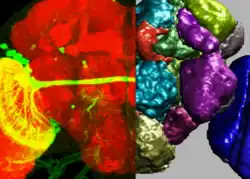

Volume segmentation

- blue: pulmonary arteries

- red: pulmonary veins (and also the abdominal wall)

- yellow: the mediastinum

- violet: the diaphragm

Image segmentation is a manual or automatic procedure that can be used to section out large portions of the volume that one considers uninteresting before rendering, the amount of calculations that have to be made by ray casting or texture blending can be significantly reduced. This reduction can be as much as from O(n) to O(log n) for n sequentially indexed voxels. Volume segmentation also has significant performance benefits for other ray tracing algorithms. Volume segmentation can subsequently be used to highlight or expose[14] structures of interest.